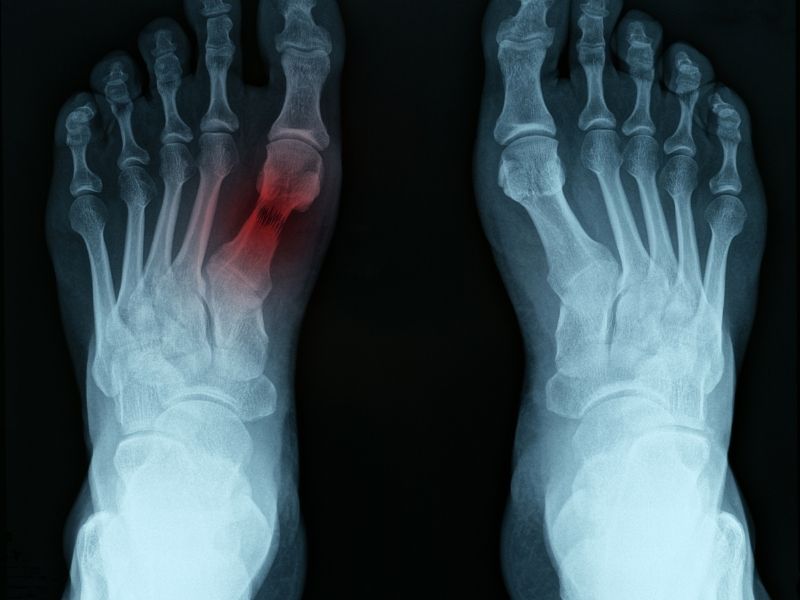

Hiç ayağınızın tepesinin üzerine ağır bir kutu düşürdünüz mü? Veya, kazara küçük bir deliğe basıp, ayağınız bükülerek basıp düştünüz mü; Bu iki sık rastlanan kaza, orta ayağın, kırık ve çıkığıyla sonuçlanır ve bu durum Lisfranc kırıkları olarak tanımlanır. Bu kırık, ismini, bu incinmeyi ilk kez tanımlayan, Fransız bir doktor olan Jacques Lisranc' dan almıştır.

Lisfranc yaralanmaları, orta ayakta, ayak bileği ve ayak parmakları arasında yer alan bir grup küçük kemiğin şekillendirdiği, ayağın tepesinde bir kavsin üzerinde meydana gelir. Bu küçük kemik grubundan, beş uzun kemik (metatarslar) ayak parmaklarına uzanır. İkinci metatars da sabitleştiren bir kuvvet gibi etki ederek küçük kemik sırasının altına uzanır.Kemikler, bağ dokuları (ligamentler) tarafından ayağın çaprazına ve altına doğru her iki yönde de yerlerinde tutulurlar. Her nasılsa birinci metatarsı ikinci metatarsa bağlayan bağ dokusu yoktur. Düşme sırasında ayağı kıvrılması, kemiği kırabilir veya kemik yerinden çıkar (dislokasyon).

Lisfranc kırık-çıkıkları sıklıkla burkulmalarla karıştırılır. Ayağın üstü şişebilir ve ağrı olabilir. Eğer incinme şiddetli ise, ayağınızın üzerine basamayabilirsiniz. Lisfranc incinmelerini röntgende görmek sıklıkla zordur. Tanımlanmayan Lisfranc incinmelerinde, eklem dejenerasyonu ve kasların içindeki sinirlerin ve kan damarlarının tahribatıyla gelişen basıncın, neden olduğu kompartıman sendromu gibi komplikasyonlar olabilir. Ayak burkulması için standart bir tedavi (istirahat, buz uygulaması ve ayağı kaldırma) bir veya iki gün içersinde ağrı ve şişliği azaltmıyorsa doktorunuza ortopedi uzmanına danışmasını söyleyin.